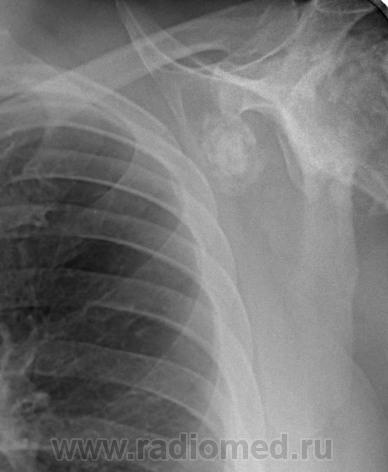

Пациент 60 лет, при прохождении проверочной флюорографии  обнаружены изменения со сторны плечевых суставов.Водитель троллейбуса.Страдает избыточной массой тела, люмбальгией, артороз коленных суставов.Непосредственно жалобы на плечевые суставы в медицинских документах не отражены. Какое будет мнение у коллег?

Пациент жалоб со сторны плечевых суставов не предъяляет и не помнит что бы когда- то что то беспокоило.Данных за сирингомиелию нет.

Александр, конечно надо доснять плечевые суставы... Из того, что есть: видимые отделы плечевых костей выглядят довольно симметрично, хотя слева и похуже, думаю - артроз. Весьма настораживает левая лопатка на предмет хондросаркомы

Снимки плечевых суставов.

Уважаемый Александр, приходиться признать, что на цифровой рентгенограмме легких изменения плечевых суставов видны лучше, чем на "обрезаных" и недоэкспонированых снимках суставов. По имеющимся данным могу только сказать, что деф. артроз с кистовидной перестройкой структуры есть. Под хрящевой опухолью (возможно - хондросаркома) левой лопатки я имела в виду тень, отмеченую красными стрелками, которая в поле снимка не вошла. Моя вина - в силу специфики работы такие узкоформатные снимки давно были вредными, т.к. очень часто патология остается за пределами снимка. Остается рекомендовать рентгенография левой лопатки в прямой передне-задней и косой проекциях, а лучше - КТ...